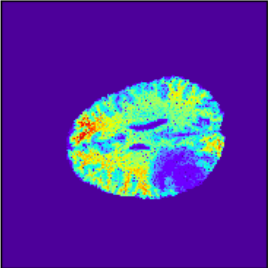

To illustrate the performance of the proposed technique for clinical applications, MR images were chosen. The performance of the technique was tested by registering multi-modal MR image pairs. In a clinical setup, it is common practice to register images or volumes acquired from different imaging modalities or MR sequences. Figure 3 illustrates the degree of overlap between moving images (a) T2 and (f) T1 weighted sequence on fixed images (b) T2 and (g) T2 weighted sequence respectively. It was observed using the registration proposed in this manuscript, the dice score improved from 0.44 (prior to registration) to 0.91 (post registration) for multimodal sequences. On the BraTs data, figure 4 (a-d) illustrates the performance of our method based on other metrics such as Dice, SSMI, MI, and MSE respectively. As the key points were generated by utilizing only the feature maps of the initial two layer of the network, the spatial dimension of the data has little impact on the performance. Unlike other CNN based technique which considers the entire image for estimating the transformation parameters, our method requires CoMs which reduces the dimensionality from (m n n) to (m 2), where m denotes the number of feature maps and n is the pixel dimension of the feature map. This aids in lowering execution time drastically. The proposed pipeline also consists of an uncertainty estimator. uncertainty maps illustrated in all the above examples show the region of higher variance in registration, which in turn suggests surgeons/ observers to make better decisions. Pixel region with red color indicates the larger variance region while blue indicated low variance region. For example in figure 3 (e) shows that the central region of the brain has higher pixel-wise variance as compared to the outer part of the brain. The performance of the algorithm on volumes on the same modality is illustrated in figure 3 (a-e)